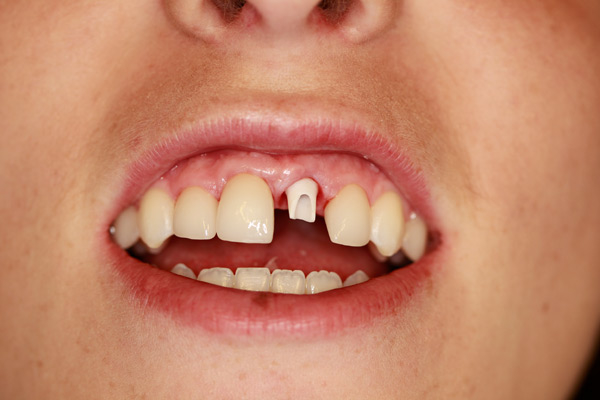

Case Study 7

Problem: This young patient lost her front tooth. She also had a dark tooth that was treated with a root canal.

Plan: Our plan… placed an implant then molded the tissue for a few months to get the best appearance. A zirconium abutment was used to restore the tooth and veneers on the other three front teeth.

Creating beautiful smiles.